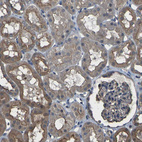

Immunohistochemical staining of human testis shows moderate to strong cytoplasmic positivity in cells in seminiferous ducts.